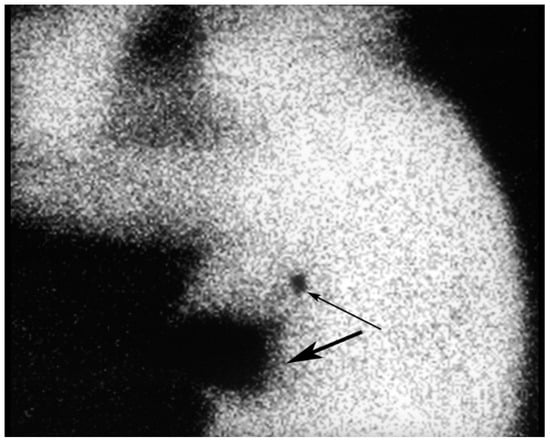

Figure 12. An injection site in the upper outer quadrant of the right breast (large arrow) is seen adjacent to a low axillary SLN (small arrow).

In another study, patients were injected with 1.0 mCi of Tc-99m-sulfur colloid (unfiltered) in the subareolar area of the tumor-bearing breast and an injection of 2 to 5cc of isosulfan blue was performed around the tumor. Thirty-two percent of the patients had history of previous excisional breast biopsies. Of the 69 lesions, 62 (89.9%) had SLNs located with the blue dye and 65 (94.2%) had SLNs located with the radiopharmaceutical. In four patients, the SLNs were not located with either method. All located SLNs were in the axilla. An average of 1.5 SLNs per patient were found in the 62 patients in which the SLNs were located with both methods and 23.2% of the SLNs had metastatic disease. All four patients in whom no SLNs were located with either method had undergone prior excisional biopsies. The authors concluded that subareolar injection of Tc-99m-sulfur colloid is as accurate as peritumoral injection of blue dye. Subareolar injection of the radioisotope avoids the problem of overlap of the injection site with the radioactive SLN (Figure 12), particularly in upper outer quadrant breast lesions [29].

Diffusion of radioactivity injected around the tumor into the breast may preclude identification of a SLN near the tumor site due to radioactive shine-through. Shine–through occurs in lesions in the upper outer quadrant close to the axilla. SLNs located less than 115 mm from the injection site may be poorly localized secondary to high background activity. Another pitfall in lymphoscintigraphy is radiopharmaceutical within the needle hub simulating a lymph node.